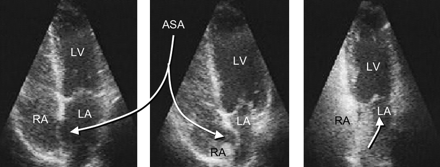

| Figure 4. Documentation

of a PFO and an atrial septal aneurysm (ASA) by TTE. The floppy

part of the septum primum undulates between the right atrium

(RA, left) and the left atrium (LA, center). The bubble test

shows bubbles passing into the LA toward the left ventricle

(LV). It is important to make sure that the bubbles cross through

the PFO and not through pulmonary shunts. Bubbles crossing

through pulmonary shunts appear usually late (after several

heart beats) in the LA, irrespective of the Valsalva maneuver.

They emerge from anywhere in the left atrium and are usually

devoid of the larger bubbles seen in the right atrium.